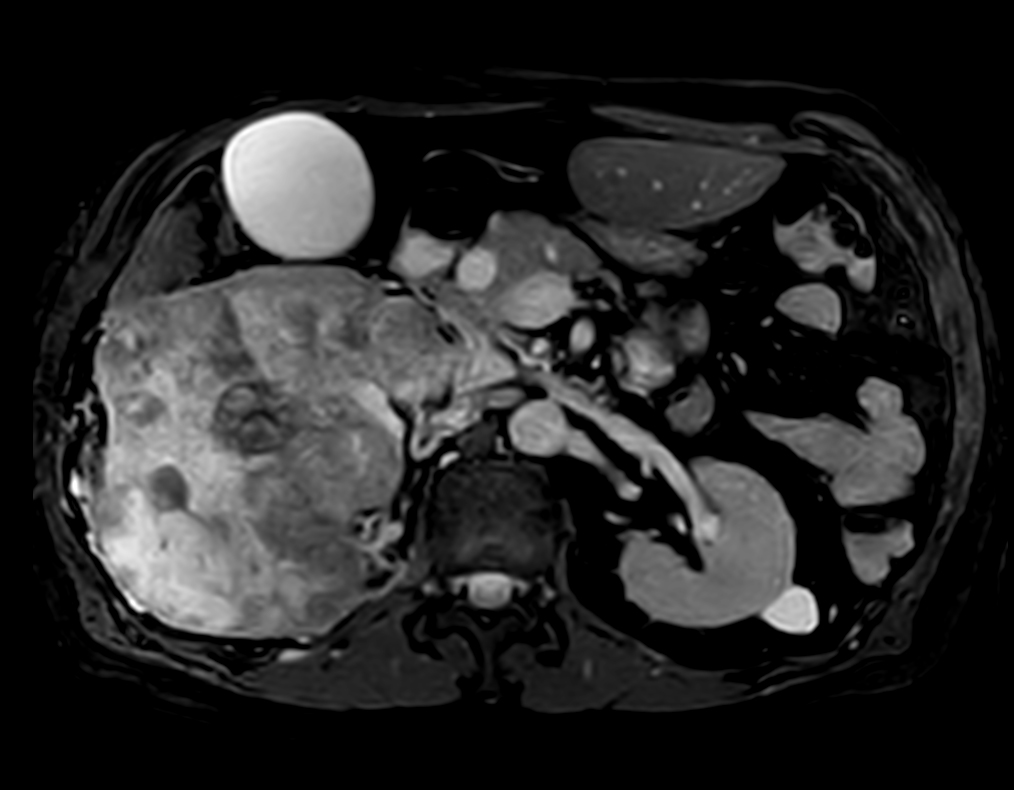

Patient with kidney tumor. ExamCard includes Compressed SENSE to shorten the breath hold time, VitalEye for touchless respiratory sensing, mDIXON XD FFE to acquire up to four image types in one single scan, DWIBS to achieve high contrast between background and lesions and bTRANCE for non-contrast time-resolved imaging.

bTFE - VitalEye Compressed SENSE